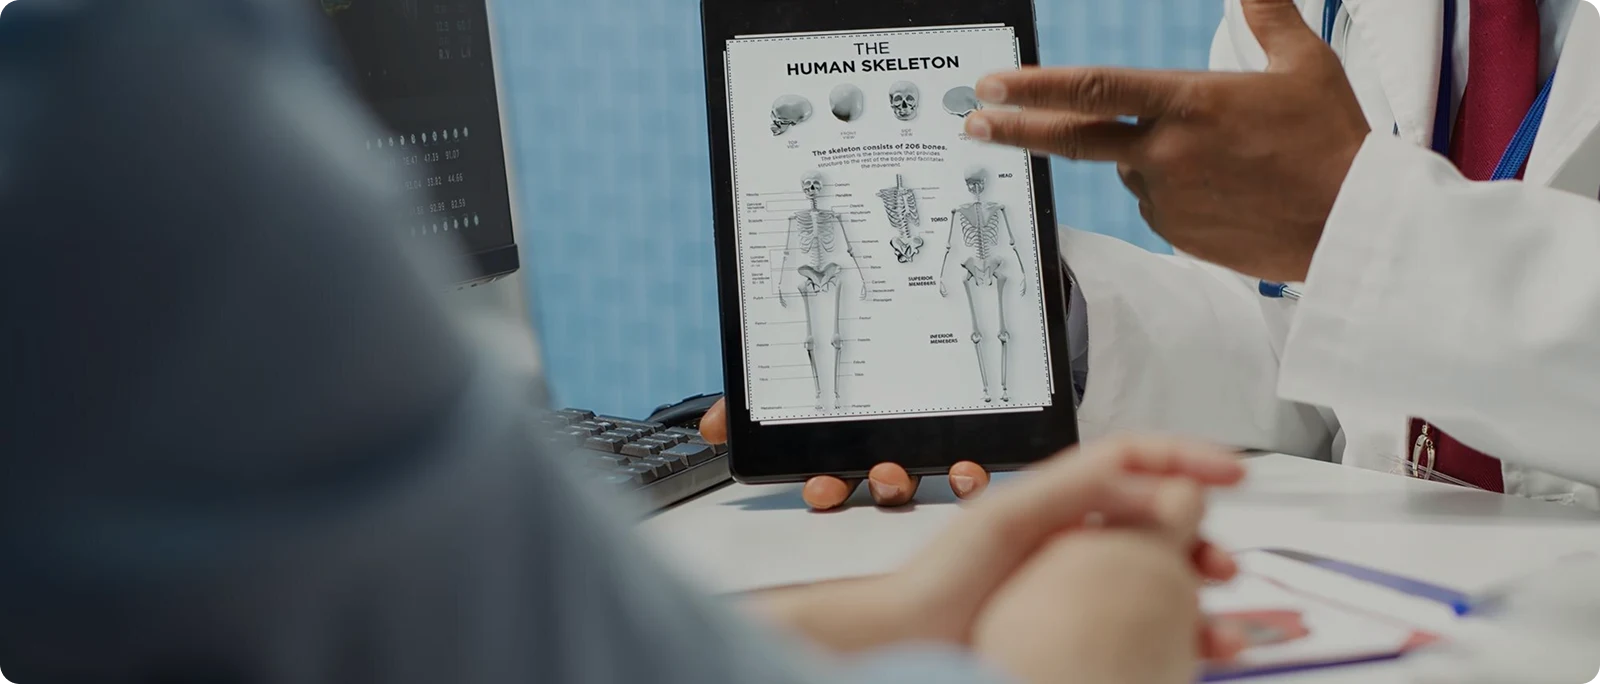

Evaluation at Bangalore Back

I begin with a clean slate—no assumptions. We review pre‑ and post‑operative MRIs, operative notes, implant position, and alignment. We add dynamic X‑rays for movement, CT for fusion/implant integrity, and MRI with metal‑artifact reduction when needed. Equally important are posture analysis, core stability testing, and rehabilitation review. This structured walk‑through reveals the true driver of pain and guides the plan.